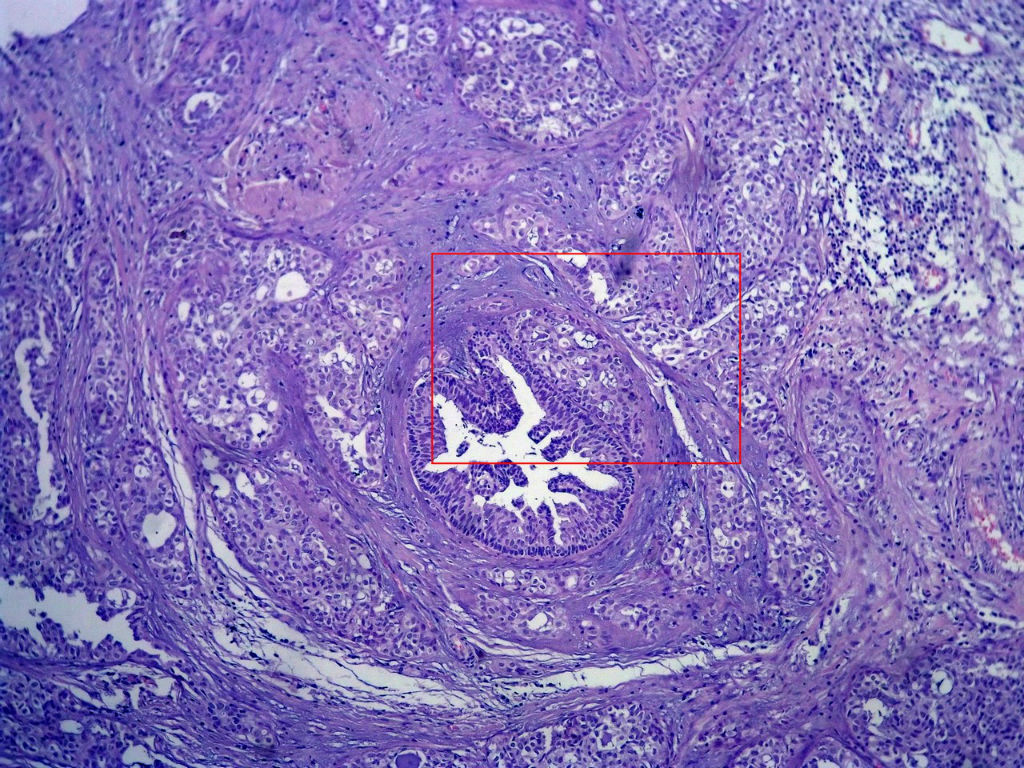

今天的一例术中冰冻。女,49岁,乳腺肿块。人气不旺,换个标题

腺病?癌?其他?(12楼常规,24楼免疫组化及会诊结果)图1

标签:浸润性导管癌 分泌癌 硬化性腺病

导管是乎可见双层上皮,部分上皮增生并有一定异型,考虑硬化性腺病,待石蜡。

导管可见双层上皮,部分上皮增生并有一定异型,考虑硬化性腺病

腺体与腺体之间的对比差异太大,不放心,不除外是癌,如果是我的病例,再次取材冰冻

后取的恶性特征明显多了,神经内分泌癌?

浸润性导管癌

浸润性导管癌。冰冻切片的诊断是很困难,直接诊断癌风险很大,但是在明显正常的导管间这种成片、成巢有腔的细胞团块也不是良性的表现,有的还似乎有围绕正常导管生长的倾向。诊断ADH还可以,但是不能归到任何一种DCIS的生长方式里。这例值得我好好学习。

Looks like IDC?

Do you have myoepithelial stains?